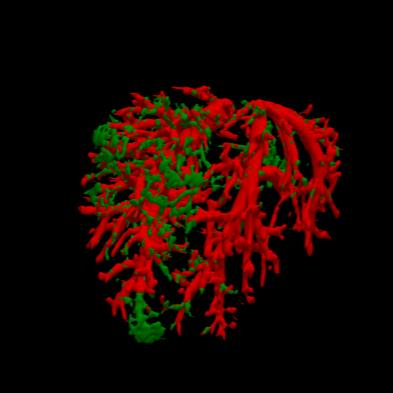

Manually segmenting the hepatic vessels from Computer Tomography (CT) is far more expertise-demanding and laborious than other structures due to the low-contrast and complex morphology of vessels, resulting in the extreme lack of high-quality labeled data. Without sufficient high-quality annotations, the usual data-driven learning-based approaches struggle with deficient training. On the other hand, directly introducing additional data with low-quality annotations may confuse the network, leading to undesirable performance degradation. To address this issue, we propose a novel mean-teacher-assisted confident learning framework to robustly exploit the noisy labeled data for the challenging hepatic vessel segmentation task. Specifically, with the adapted confident learning assisted by a third party, i.e., the weight-averaged teacher model, the noisy labels in the additional low-quality dataset can be transformed from "encumbrance" to "treasure" via progressive pixel-wise soft-correction, thus providing productive guidance. Extensive experiments using two public datasets demonstrate the superiority of the proposed framework as well as the effectiveness of each component.